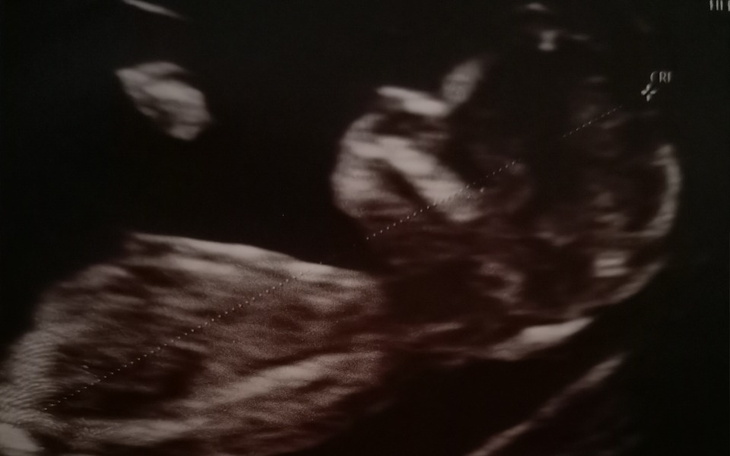

Witam serdecznie wszystkie osoby odwiedzające tą zbiórkę. Opowiem Wam swoją historię. Spodziewam się z partnerem córeczki, niestety los pokrzyżował nam plany, w jednej chwili cały świat runął. U naszego dziecka stwierdzono na echu serca poważne złożone sinicze wady serca - przełożenie wielkich pni tętniczych z ubytkiem podpłucnym w przegrodzie międzykomorowej. Na dodatek jest duże ryzyko koarktacji lub hipoplazji. Jesteśmy załamani diagnozą, lecz wiemy , że musimy walczyć do końca, do utraty tchu. Czekają nas bardzo ciężkie chwile,pełne stresu, wiele wizyt w specjalistycznych placówkach, poród i operacja ratująca życie w specjalistycznym szpitalu i częste kontrole lekarzy jeśli operacja się powiedzie. Niestety w dzisiejszym świecie wszystko wiele kosztuje, a my boimy się o przyszłość,jak to dalej będzie. W związku z tym założyliśmy zbiórkę zanim jeszcze córeczka pojawi się na świecie - przeznaczona będzie na lepszy start- żeby nie zabrakło opieki u dobrych lekarzy i inne niezbędne wydatki związane z jej zdrowiem. Mamy nadzieję ,że znajdą się osoby o złotym sercu, które nas wesprą, wierzymy że dobro do Was wróci.